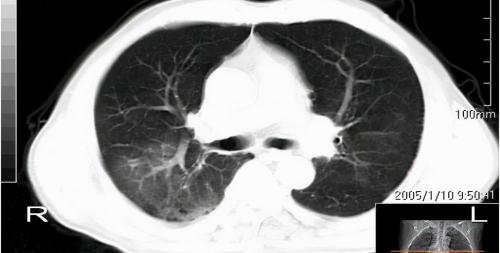

肺结核是呼吸道常见的传染性疾病,气管镜是诊断肺结核非常常用,也是非常重要的一种方法。但是,仅仅依靠气管镜还不能完全地诊断肺结核,还需要结合一些其他的检查来进行综合分析和判断。比如肺部的ct、痰找抗酸杆菌、痰培养、tbdna、结核菌素实验、淋巴细胞斑点试验等等。

如果经过综合检查和分析,诊断为肺结核的话,就一定要积极地给予治疗。首先就是规范的抗结核治疗,抗结核治疗过程中要注意抗结核药物的不良反应,一旦发生要及时处理,同时还要加强营养支持以及对症治疗。还要定期复查肺部ct等等这些指标来观察治疗效果。平时患者要注意休息,不能抽烟,不能饮酒。

2、检查前患者,必须拍摄X线正侧位胸片,必要时做胸部CT以便确定病变的部位;